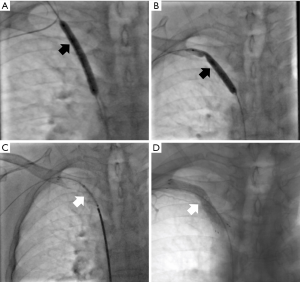

| Representative pictures of sharp needle recanalization of CVO. (A ...

Segmented sharp recanalization. (A) Right SV obstruction with ...

Sharp puncture with the TIPS set: (A) at the distal circumference of ...